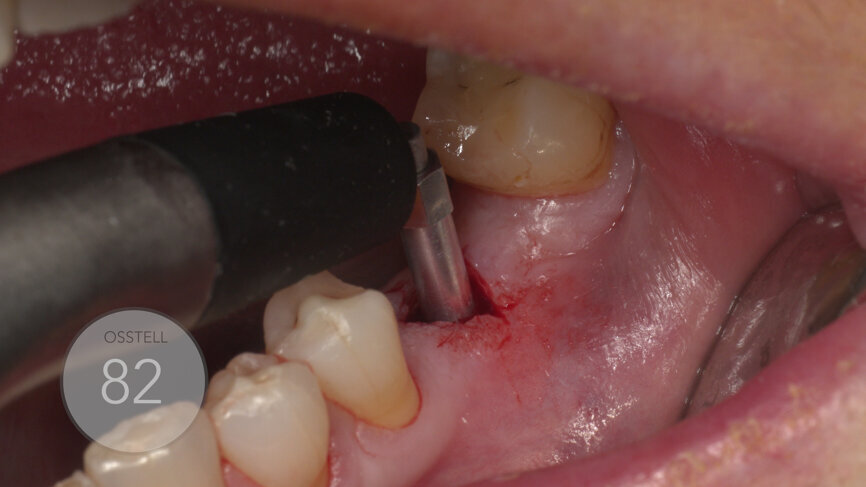

The ISQ level was determined with the Osstell unit. After connecting a Type 54 SmartPeg, a score of 82 was obtained (Fig. 12). The decision to employ an immediate loading protocol has to take account of the surgeon’s personal experience and skills, the insertion torque value, the ISQ levels and the medical and dental characteristics of the patient. In this case, all these parameters were evaluated as excellent, and the immediate loading protocol was selected.